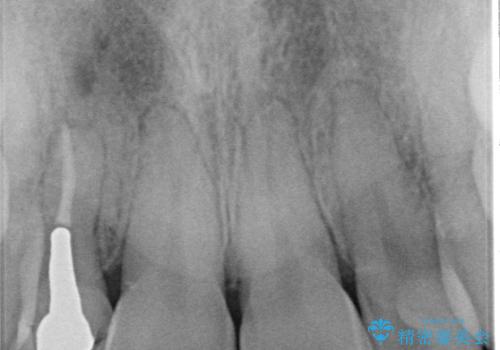

被せ物と歯の境の位置が歯肉の上に設定されており、それによって審美障害が起きていました。

歯と被せ物の境を歯肉縁下0.5㎜に設定して形成を行いオールセラミッククラウン(スペシャル)で治療を行いました。